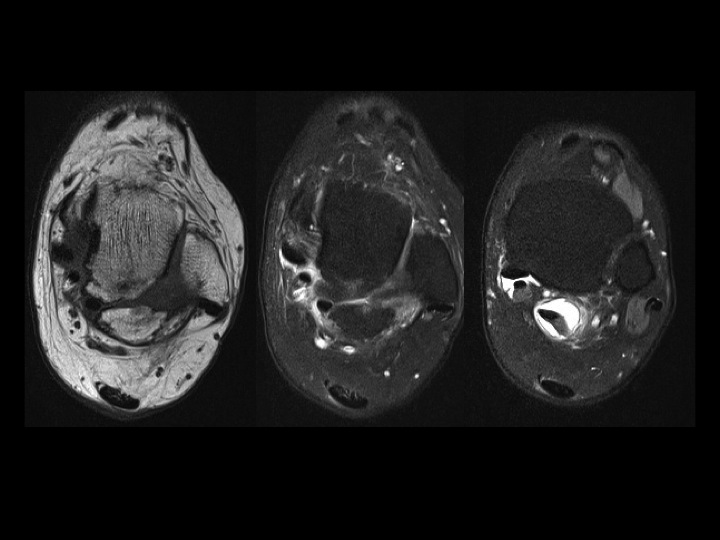

42 yr old female with 8 months burning lateral foot pain after ankle surgery

First 2 slides show an enormous os trigonum with posterior ankle impingement and associated FHL tenosynovitis. Latter 3 post op slides should extensive scarring obscuring fat planes in the region of the sural nerve which is presumably encased. Reference article.

sural nerve ( RID7347 )